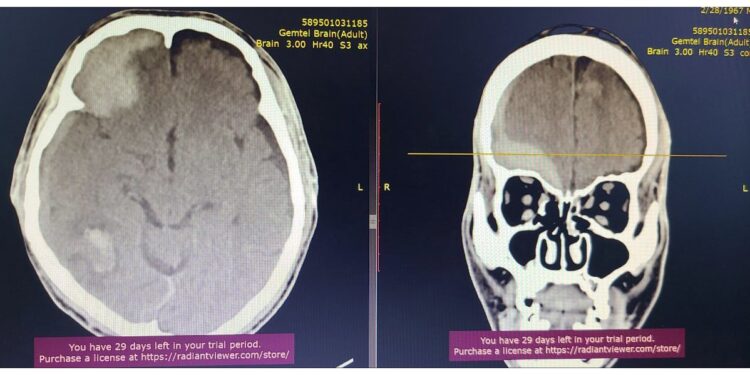

Гэмтэл Согог Судлалын Үндэсний төв Монголд анх удаа шагайн хиймэл үе солих мэс заслыг амжилттай нэвтрүүлсэн талаар бид өмнө нь мэдээлж байсан. Тэгвэл энэ удаад тус эмнэлгийн Гавал тархины гэмтлийн тасгийн эрхлэгч Л.Дагвадорж, их эмч Ж.Төгөлдөр, Б.Лхамсүрэн, Г.Ариунболд нарын мэс заслын баг Монголд анх удаа "Suction bovie" багажийн тусламжтайгаар гавал тархины хүнд гэмтэлтэй үйлчлүүлэгчийн гавал тархины хатуу хальсан доорх цусан хурааг дурангийн аргаар авах мэс заслыг амжилттай хийж нэвтрүүллээ.

Энэхүү орчин үеийн дэвшилтэт мэс заслыг нутагшуулснаар өвчтний биед хөнөөл багатай, жижиг зүслэгтэй, гавлын ясны дутмагшил бага үүсэх, хөдөлмөрийн чадвар алдалт бага зэрэг олон ач холбогдолтой юм.